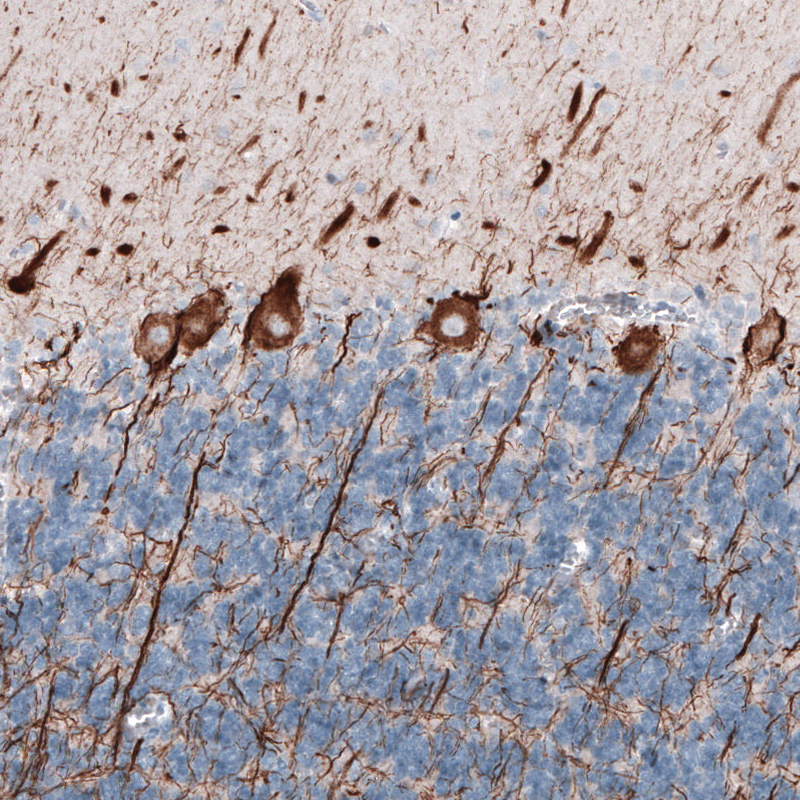

Immunohistochemical staining of human cerebellum shows strong cytoplasmic immunoreactivity in cell bodies and proximal dendrites of Purkinje cells.